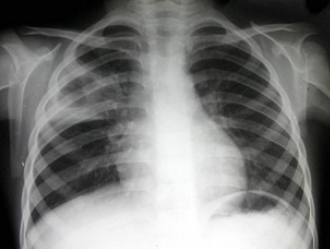

33、单项选择题

女,10岁,高热、咳嗽一天,血象:中性多形核粒细胞高度增多及核左移,血沉加速,痰中查到大量结核杆菌。结合图片,最可能的诊断是()

A.右上肺干酪性肺炎

B.大叶性肺炎

C.支气管扩张

D.小叶性肺炎

E.葡萄球菌性肺炎